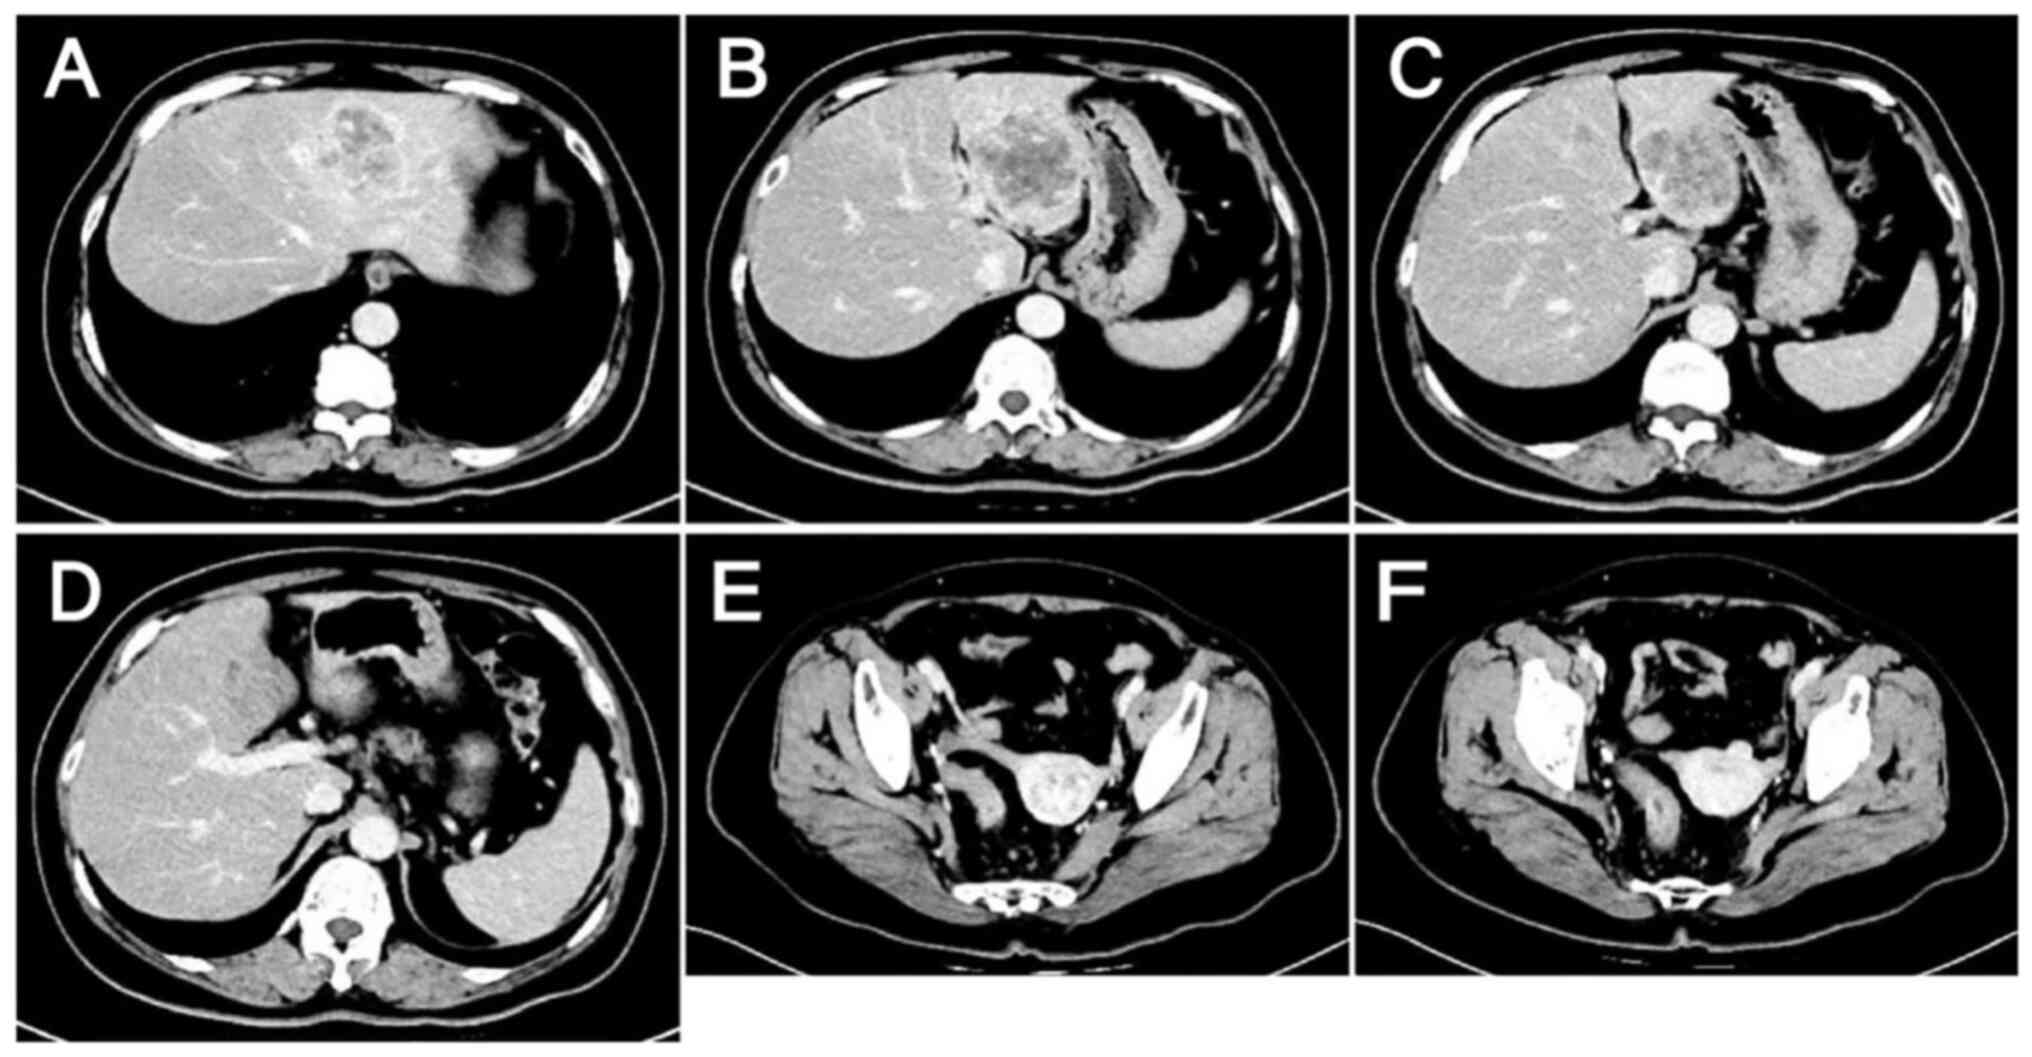

EGFR inhibitor therapy was not considered due to the NGS result and the evidence suggesting that patients with HER2-positive CRC are highly resistant to EGFR inhibitors (11,12). Furthermore, targeted bevacizumab therapy was not started because hemorrhage is one of the most serious adverse effects of bevacizumab and the patient had persistent hematochezia. In light of the recent developments in CRC research and the financial circumstances of the patient, single-agent anti-HER2 therapy combined with a modified FOLFOX6 regimen was selected as the subsequent treatment, in which the doses of chemotherapeutic agents were adjusted and administered on a 3-week cycle. The patient received six cycles of trastuzumab 450 mg + FOLFOX, with the latter comprising oxaliplatin 150 mg + leucovorin calcium 600 mg + fluorouracil 0.625 g by injection + fluorouracil 4 g by continuous intravenous drip. These agents were administered on 41 days post admission, 62 days post admission, 83 days post admission, 108 days post admission, 134 days post admission, and 157 days post admission. During treatment, the tumor marker levels gradually decreased (Fig. 4), and computed tomography (CT) and magnetic resonance scans of the liver indicated a marked reduction in the size of the tumor lesions (Fig. 6, Fig. 7, Fig. 8, Fig. 9). This was evaluated as a partial response.

Lesions after 1 cycle of anti-HER2

therapy combined with chemotherapy as evaluated by computed

tomography on December 13, 2023. (A-D) Metastatic liver lesions:

Lesions appear smaller compared with those on November 10, 2023. (E

and F) Colon lesions: Thickening of the sigmoid-rectal wall is

reduced, and the enlarged surrounding lymph nodes are slightly

smaller than they were on November 10, 2023.

Figure 6.

Lesions after 1 cycle of anti-HER2 therapy combined with chemotherapy as evaluated by computed tomography on December 13, 2023. (A-D) Metastatic liver lesions: Lesions appear smaller compared with those on November 10, 2023. (E and F) Colon lesions: Thickening of the sigmoid-rectal wall is reduced, and the enlarged surrounding lymph nodes are slightly smaller than they were on November 10, 2023.

Lesions after 4 cycles of anti-HER2

tomography on February 16, 2024. (A-D) Metastatic liver lesions:

Lesions are smaller compared with those on December 13, 2023. (E

reduced and the surrounding lymph nodes are slightly smaller than

they were on December 13, 2023.

Figure 7.

Lesions after 4 cycles of anti-HER2 therapy combined with chemotherapy as evaluated by computed tomography on February 16, 2024. (A-D) Metastatic liver lesions: Lesions are smaller compared with those on December 13, 2023. (E and F) Colon lesions: Thickening of the sigmoid-rectal wall is reduced and the surrounding lymph nodes are slightly smaller than they were on December 13, 2023.